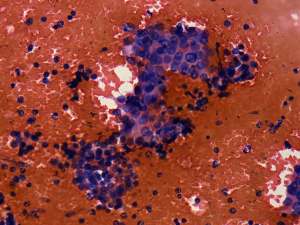

Aspiration cytology: There was no colloid in the background. Follicular cells occurred in microfollicles and compact clusters. Lymphocytes were also present in smaller number, even mixed with follicular cells. Grooves were found occasionally.

Combined sonographic-cytological diagnosis: Chronic lymphocytic thyroiditis. The risk of malignancy is not greater than 1%.

Histopathology disclosed Hashimoto's thyroiditis with several cystic areas but without any nodule.